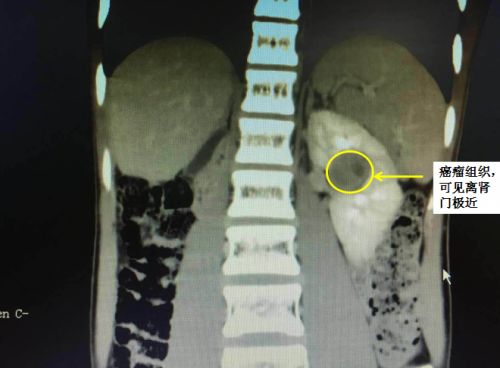

影像资料上可以清楚地看到肿瘤位于左侧肾门附近,周围血管丰富。

2018年12月25日,小昱因肿瘤复发入住捷克论坛 泌尿三科。完善术前检查后,医生考虑小昱目前为孤立肾(右肾已切除,仅剩左肾)肿瘤复发转移,且肿瘤为完全内生型,被包裹在肾脏内,且位于肾门血管旁,更致命的是孤肾合并有肾功能不全,稍有不慎便可能导致术后肾功能完全丧失,甚至需要接受肾移植挽救生命。

12月27日,段燚星教授、郭玺博士手术团队为小昱施行肠粘连松解术+左肾游离旋转+术中B超定位+左肾肿瘤肾部分切除术+肾静脉修补术+肾盂肾盏修补重建术。手术过程犹如给红枣去核,完整去除肿瘤约3x3cm大小。手术耗时3小时,出血量仅10ml,手术操作可谓“快、准、狠”,手术难度及精细程度也是空前。